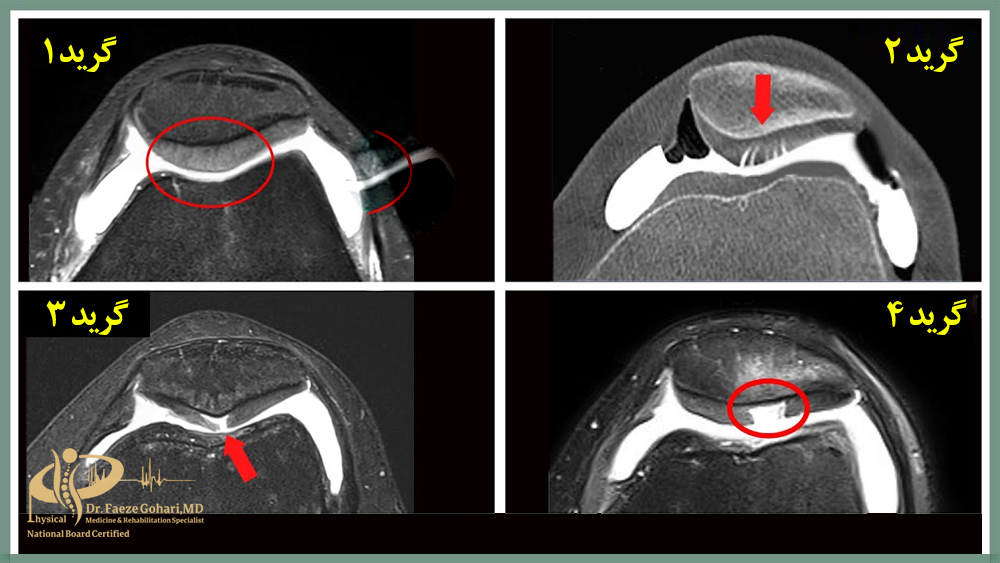

کندرومالاسی کشکک

پیآرپی (پلاسمای غنی از پلاکت) در درمان کندرومالاسی کشکک، بهویژه در مراحل اولیه تا متوسط (گرید ۱ تا ۳) که غضروف هنوز توانایی ترمیم دارد، مؤثر شناخته شده است. این روش بهویژه در افرادی که به دلیل فعالیت زیاد مانند دویدن یا ورزش دچار این مشکل شدهاند، نتایج قابلتوجهی نشان داده است.

عواملی مانند روش تهیه PRP و تعداد جلسات تزریق نیز در میزان اثربخشی آن نقش دارند. همچنین، اثرات درمانی پیآرپی در مقایسه با تزریق ژل (اسید هیالورونیک) ماندگاری بیشتری داشته و تا ۱۲ ماه نیز گزارش شده است.